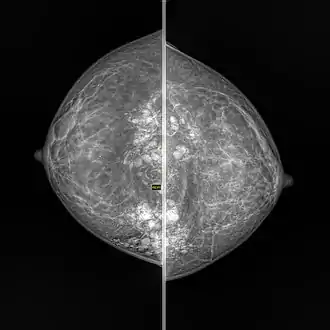

- Lymph node: Granulomatous lymphadenitis[3][4]

- Breast: Granulomatous mastitis[9][10]